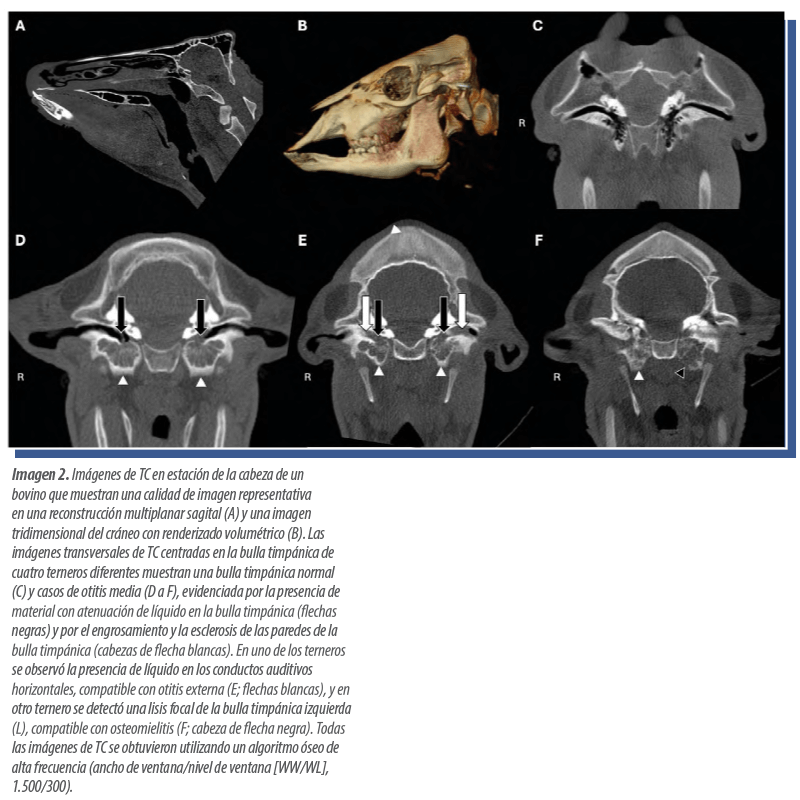

En los seis casos en los que se realizó TC de la cabeza, el hallazgo principal fue la otitis media, detectada en cuatro animales, todos ellos terneros (Imagen 2).

El diagnóstico más frecuente en las exploraciones de cabeza fue la otitis media. Este hallazgo no resulta sorprendente, dado que la mayoría eran animales jóvenes en los que las enfermedades respiratorias son frecuentes.

Diversos estudios han demostrado que las enfermedades respiratorias y la otitis pueden estar interrelacionadas, y que las puntuaciones clínicas no siempre se correlacionan adecuadamente con fases tempranas o avanzadas de otitis media o interna.

| La radiografía y la ecografía pueden emplearse para la identificación de otitis media, pero no presentan la misma sensibilidad ni especificidad que la TC, que permite determinar con mayor exactitud la extensión de la lesión y la posible presencia de osteomielitis en el hueso circundante. |